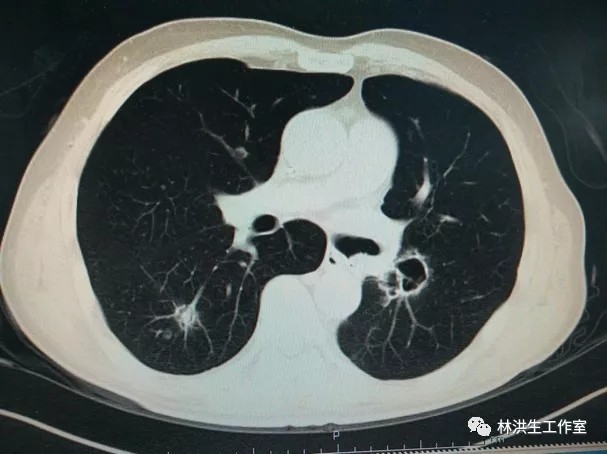

2017-10-21中药治疗后:双肺多发转移瘤大者增大至约2.6*2.3cm